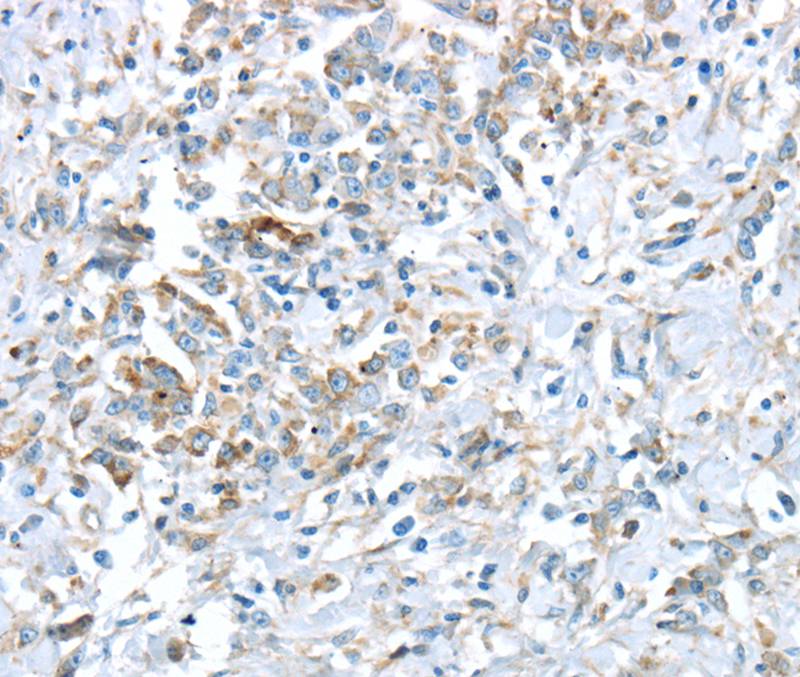

Immunohistochemical analysis of paraffin-embedded Human esophagus cancer tissue using #40403 at dilution 1/30.

Immunohistochemical analysis of paraffin-embedded Human gastric cancer tissue using #40403 at dilution 1/30.